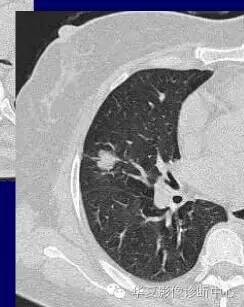

对于不好定的,不典型的一律建议抗炎后复查

如果不看边缘是否清楚,就好像癌肿

但是一看边缘就是炎性病变

大家记住了,边缘模糊的GGO首先考虑炎症